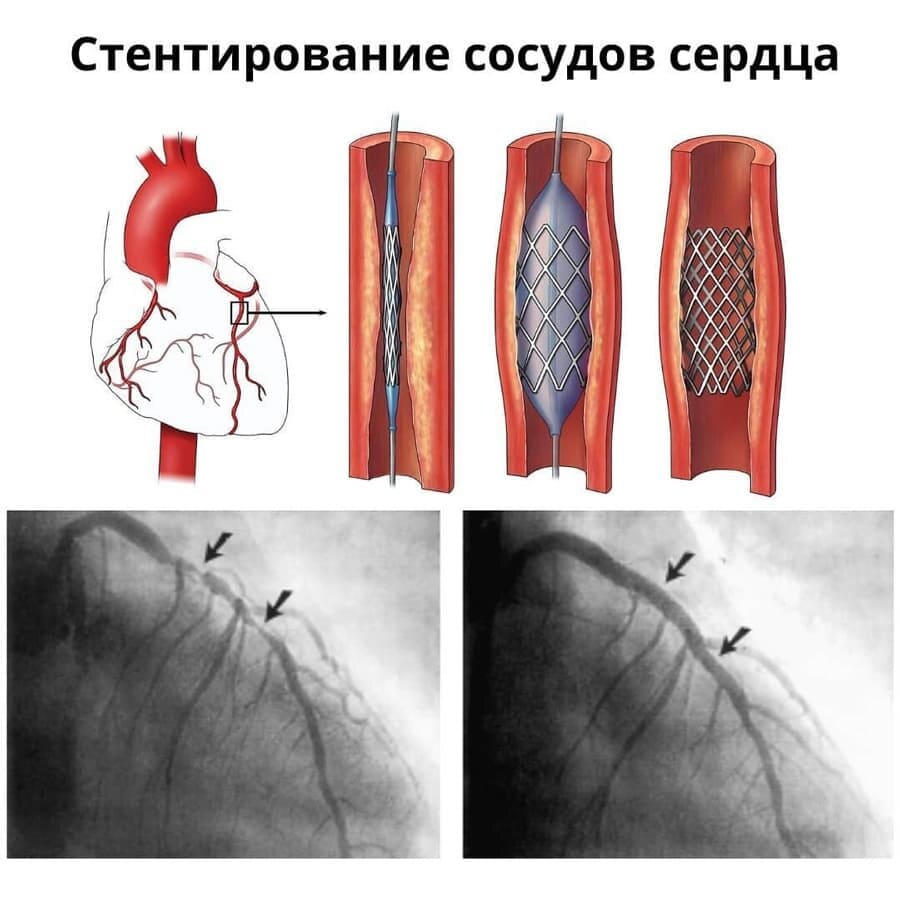

Хроническая окклюзия артерий: причины, симптомы и лечение